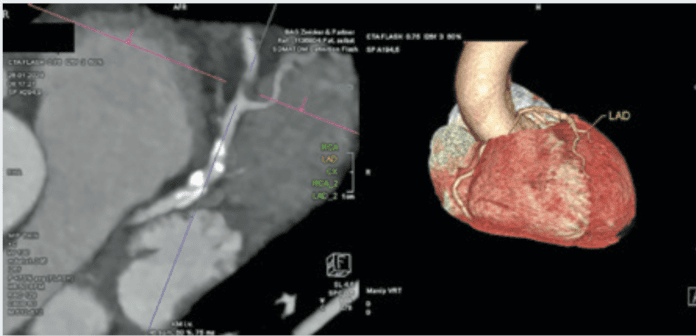

Computed Tomography (CT) Tests Provide Information on Plaque

Two CT-based tests help inform your risk of heart attack and reveal whether you need aggressive prevention, additional testing or revascularization.

Do you know how much plaque is in your coronary arteries?